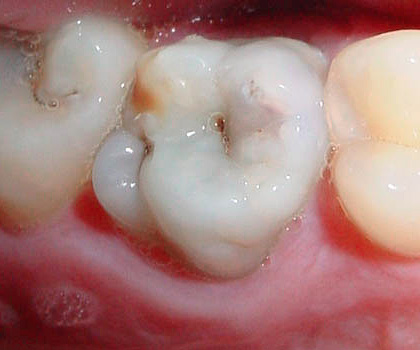

Nella maggior parte dei casi, al primo esame dei denti, le loro pareti (superfici) colpite dalla carie colpiscono. Spesso non si tratta di cavità, ma semplicemente di smalto grigio e appannato, che ha perso il suo aspetto sano a causa della demineralizzazione.

Spesso il dentista vede un "tunnel" tra i denti, ma la sonda potrebbe non passare nella cavità cariata interna nascosta a causa della densità dello spazio interdentale. Di solito, il medico mostra al paziente sfumature di smalto grigiastro nello specchio sullo sfondo della carie interna sviluppata e inizia il trattamento dei denti dopo l'anestesia.